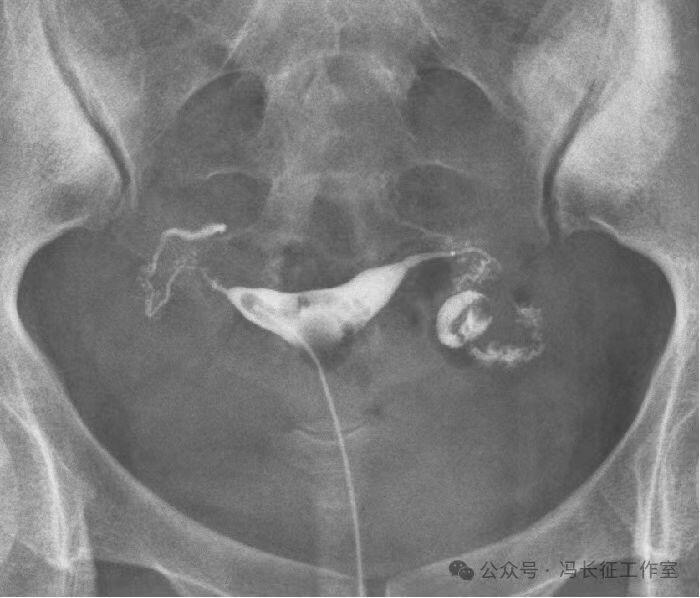

输卵管积水的子宫输卵管造影尽量包括这5个方面的描述,诊断的临床意义才最大,这样才能给好的生殖科医生有价值的建议,帮助给不孕者制定最好的助孕治疗方案。比如这例输卵管积水,峡部结节性输卵管炎(病因),交通性(积水近端是否和宫腔相通),中度(积水大小),厚壁(管壁的厚度),多囊(囊腔的多少)。

微信图片_20240220111109(1).jpg

最后诊断应该是:双侧峡部结节性输卵管炎并双侧中度、厚壁、多囊、交通性输卵管积水。